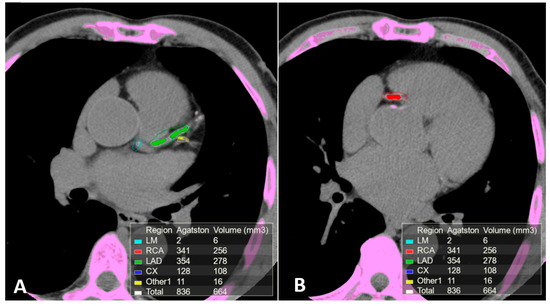

IVUS and OCT allow direct cross-sectional visualization of the coronary wall and are now considered the gold standard for in vivo imaging of coronary calcification [79,100,103]. IVUS imaging is based on ultrasound reflection by coronary calcification and is more sensitive and specific than angiography (Figure 5). Compared to OCT, IVUS has lower spatial resolution and greater penetration depth, thus provide good assessment of the entire arterial wall. However, IVUS cannot penetrate calcium, hence its assessment of plaque calcification is quantitatively expressed as arc (in degrees) and length. Calcified plaques appear echo-dense (hyperechoic) and brighter than the surrounding adventitia. Some grey-scale IVUS signal intensity features have been associated with histological features of plaque instability and high risk of CAD: plaque with ultrasonic attenuation (echo-attenuated plaque), associated with fibroatheroma containing large necrotic core; echo-lucent plaque, containing an intraplaque zone of absent echogenicity, correlated with small necrotic core; spotty calcification and calcified nodule, both associated with acute coronary events [104,105].

Figure 5.

Intravascular ultrasound (IVUS) pull-back in a symptomatic, diabetic female patient with a critical left main stenosis (A, right panel: IVUS frame corresponding to the dotted line A, left panel). Left anterior descending (LAD) presents the diffuse disease with calcific eccentric lesion (triangle arrows B and C right panel, corresponding to the dotted lines B and C left panel). Behind calcifications, shadow does not allow us to obtain complete vessel contours.

OCT uses a light source in the near-infrared range and measures the time delay of optical echoes reflected by the arterial wall, providing high-resolution cross sectional images of the plaque structure [79,110]. (Figure 6). OCT has about ten times higher axial resolution than IVUS, between 10-20 microns, and lower penetration depth, making this technique most suitable for evaluation of intraluminal structures [111]. Unlike IVUS, penetration of calcification by OCT is greater than for other tissues. Therefore, calcification thickness, area and volume may be quantified [100]. High sensitivity and specificity has been demonstrated for fibrous, fibrocalcific, and lipid-rich plaques [112]. Also, OCT is considered the only imaging modality that can directly measure TCFA and quantify the presence of macrophages and cholesterol crystal in the atherosclerotic plaque [20,104,113,114,115]. OCT imaging of contemporary presence of macrophages and microcalcifications in the same plaque with reciprocal distance smaller than 1 mm (termed co-localization), has been shown to be associated with more vulnerable plaque features [116,117]. These observations seem to indicate that OCT can provide both morphological and disease activity assessment of coronary atherosclerosis. However, the usefulness of OCT is limited by the poor penetration depth (1–2 mm) and attenuation of light transmitted through blood, thrombus and a lipid or necrotic core, all of which prevent the assessment of cross-section plaque and necrotic core area [110].

Figure 6.

Optical coherence tomography (OCT) pull-back on left circumflex. At the proximal part of the vessel, calcific deposits were detected. From distal to proximal, calcification (triangle arrows) surround almost the whole vessel circumference (B, right panel, OCT frame corresponding to the dotted line B, left panel) and more proximally (A, right panel, OCT frame corresponding to the dotted line A, left panel) another spotty, deeper and eccentric calcification.